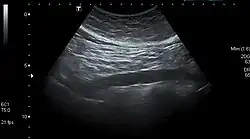

The standard aortic measurement on abdominal ultrasonography, such as used for abdominal aortic aneurysms, is between the outer margins of the aortic wall.[3]

Abdominal aorta ultrasound